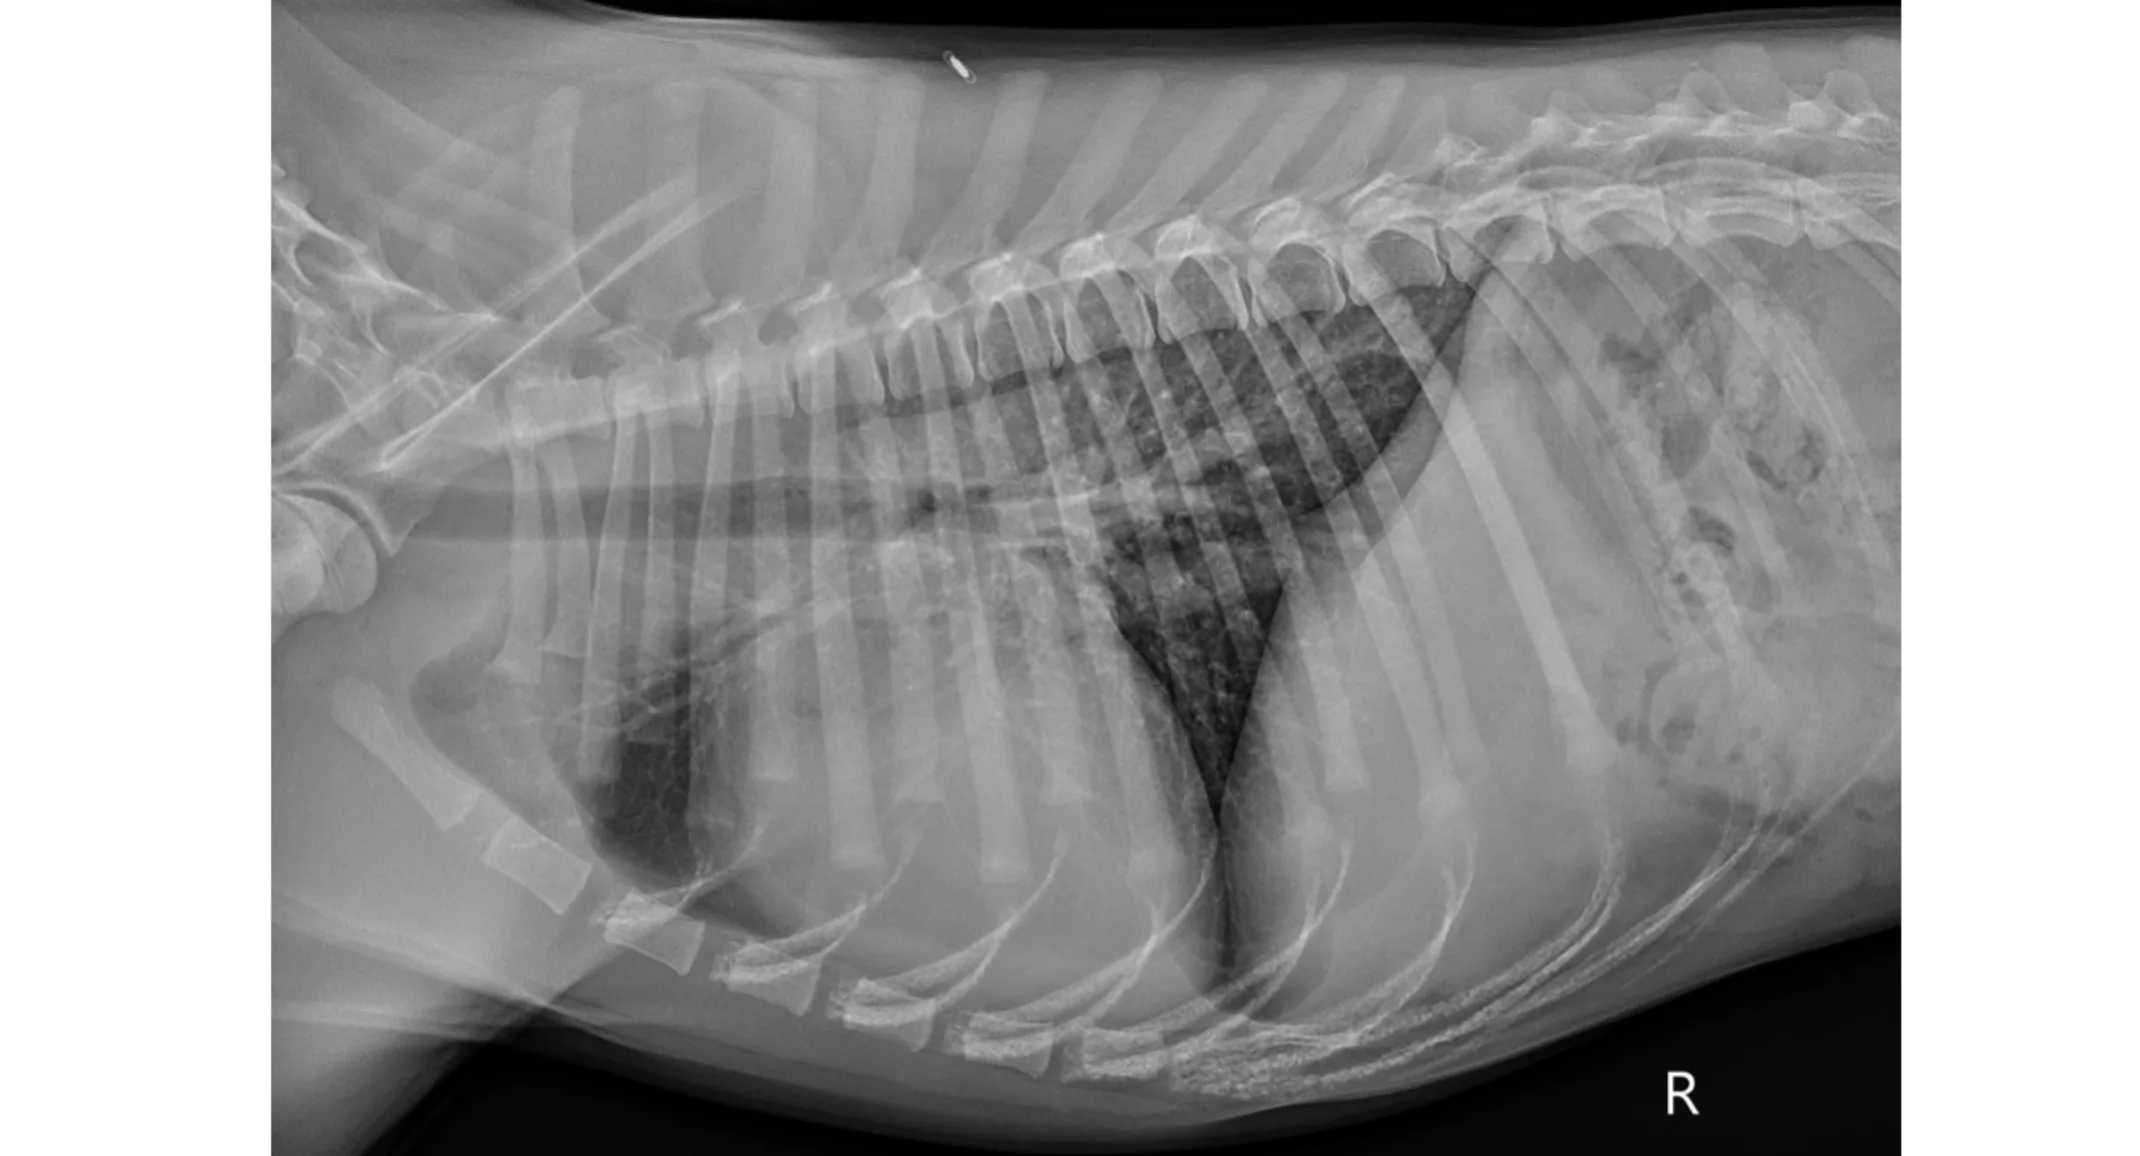

Pre-operative thoracic radiographs (Figure 1): Marked cardiomegaly with pulmonary vascular overcirculation. A mild diffuse bronchial pattern is noted. No evidence of left-sided congestive heart failure.

PICTURE: Figure 1: Pre-operative right lateral thoracic radiograph.